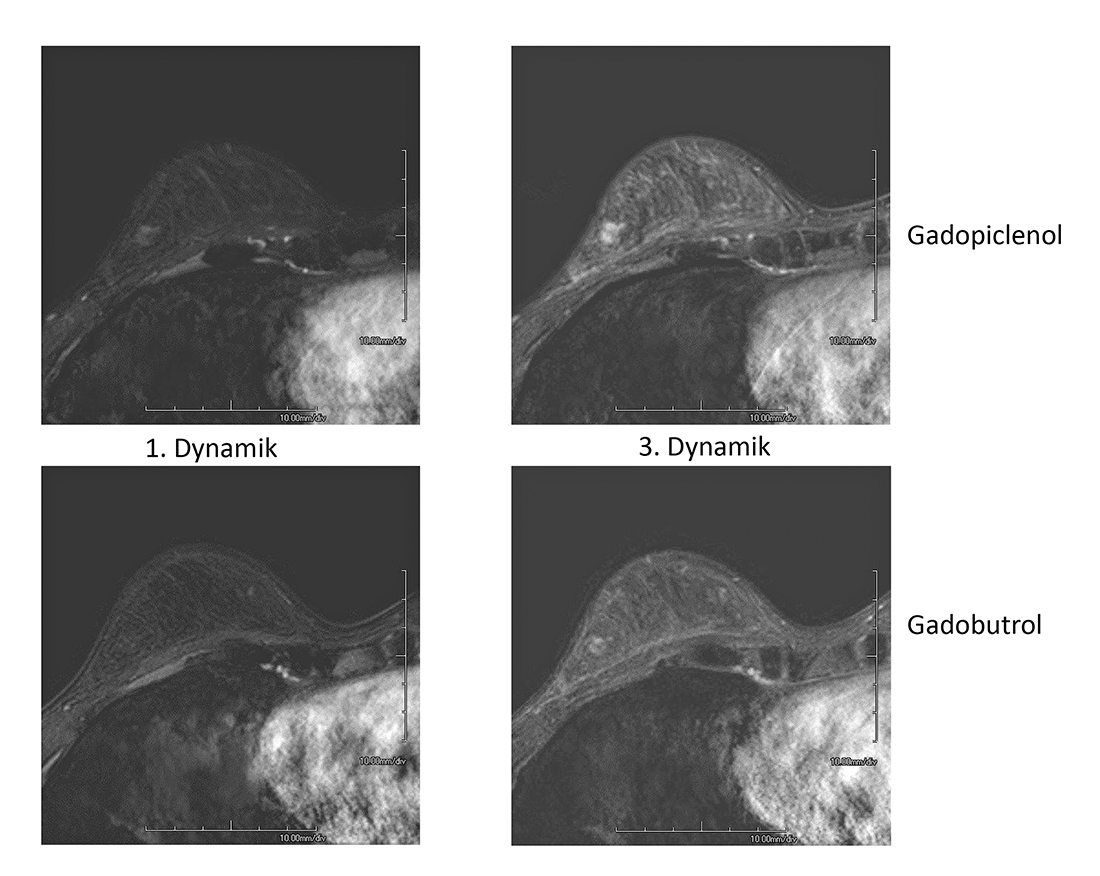

Die Europäische Arzneimittelagentur hatte gefordert, Gadolinium in der geringstmöglichen effektiven Dosis einzusetzen. Vor diesem Hintergrund engagierten sich mehrere Hersteller in der Entwicklung. Einer von ihnen ist Bracco: Gadopiclenol ist mit zwei Bindungsstellen für Wassermoleküle – statt einer – formuliert. Ein größeres Molekül sorgt für höheren Energietransfer durch eine verringerte Rotationsrate, und hydrophile Seitenketten bieten zusätzliche Interaktionsstellen für Wassermoleküle und hierdurch höhere Relaxivität. „Gadolinium zeigt bei einer Curie-Temperatur oberhalb von 20 Grad eine Veränderung von ferro- zu paramagnetischen Eigenschaften, verstärkt durch die Komplexbildner mit Außengruppen“, erläuterte Teichgräber. Dies sei mit dem neuen Kontrastmittel Gadopiclenol gelungen, mit einer Verdoppelung gegenüber Gadobutrol/Gadovist. Die Verdopplung der Relaxivität und Verstärkung des Kontrasts bringe eine Halbierung der Dosis bei besserer Sichtbarkeit mit sich. Der Jenaer Radiologe weiter: „Hiermit leisten wir auch einen wichtigen Beitrag zur planetaren Gesundheit – von der energieaufwendigen Gewinnung von Gadolinium bis hin zur Präsenz im Abwasser.“

Zu dem hochstabilen Gadolinium-Chelatkomplex wurden zwei Vergleichsstudien durchgeführt mit dem Ziel, eine Nichtunterlegenheit bei halber Dosis gegenüber Gadobutrol zu belegen. Die Phase-III-Studien zeigten eine mindestens gleichwertige Darstellung von Läsionen. Teichgräber betrachtet das neue Kontrastmittel somit als „game changer“, der sich dank der Vorteile auf dem Markt behaupten werde: „Endlich kommt hierdurch ein Innovationsimpuls.“

Die neue Struktur mit einem hochwirksamen Maß an Relaxivität beurteilte in München auch Prof. Dr. med. Thorsten Bley positiv. Die Studien hätten belegt, dass sich klarere und informativere Bilder während einer MRT-Untersuchung generieren ließen, sagte der Leiter des Instituts für Röntgendiagnostik an der Uniklinik Würzburg.